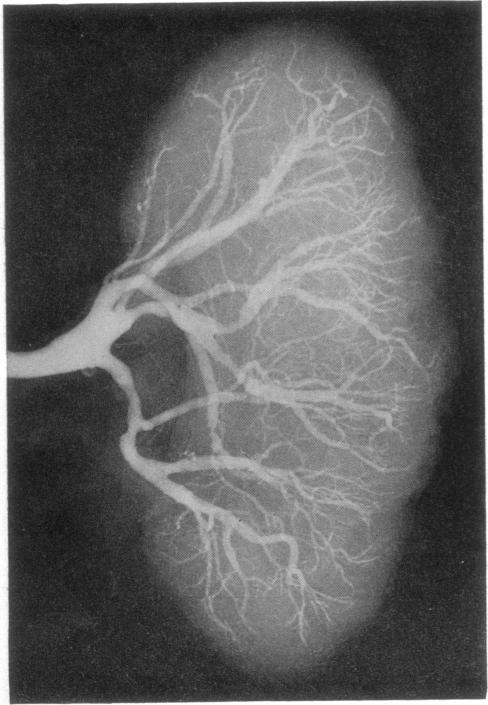

An Unusual Case of Renal Failure and Hypertension.

Br Med J. 1963 Jul 20;2(5350):167-70.